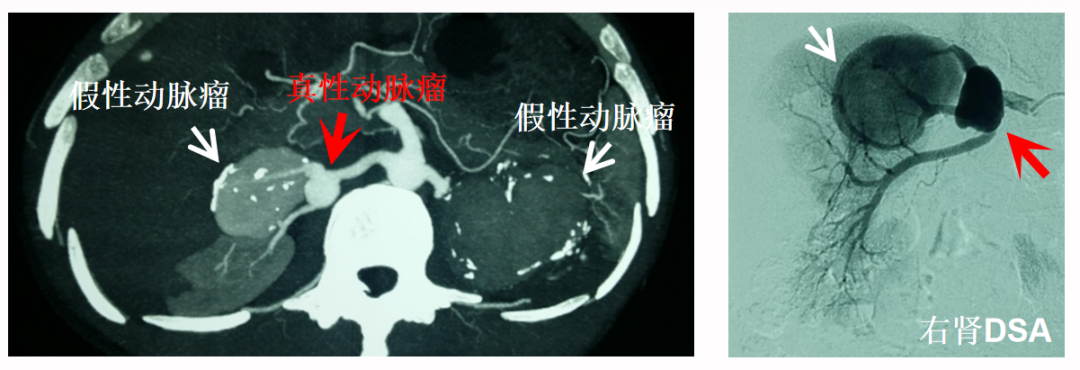

肾动脉瘤

男性,38岁,双侧复杂性肾动脉瘤